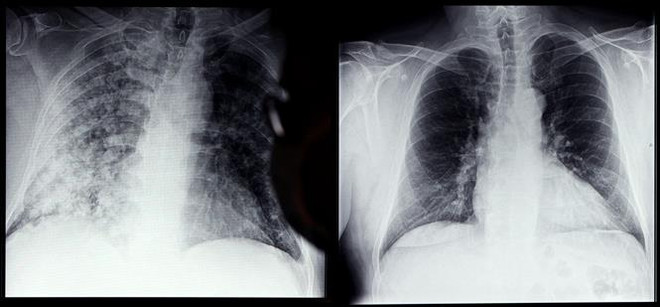

Chuyên gia WHO nêu cách xác định triệu chứng hậu COVID-19 ảnh 1Phim chụp Xquang phổi của bệnh nhân COVID-19 (trái) và phổi của người bình thường tại bệnh viện ở Magdeburg, miền đông nước Đức, ngày 28/4/2021. (Ảnh: AFP/ TTXVN)